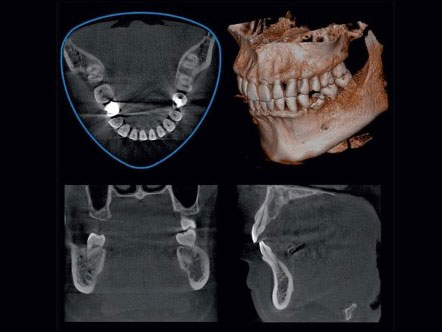

CBCT – 3D Dental Imaging

Cone Beam Computer Tomography is a specialist application for 3D dental imaging and of other maxilla facial structures.

It has a broad range of applications including oral surgery, dental implant planning and guided surgery, orthodontics, endodontics , TMJ assessment and periodontics. It offers precise diagnostics and targeted treatment planning. Resolution can be further enhanced by 360 º rotations to reduce artefacts and scatter. A 180º scanning is also possible, with a lower dose and shorter exposure time.

The eight field of views range from a small 40mm x40mm (approximately 3 teeth) to a larger 100mm x 80mm (both dental arches) subject to the clinical requirements. MORITA’s unique 3D system replaces the typical cylindrical shape with a convex triangle shape – the Reuleaux FOV thereby reducing the dose.